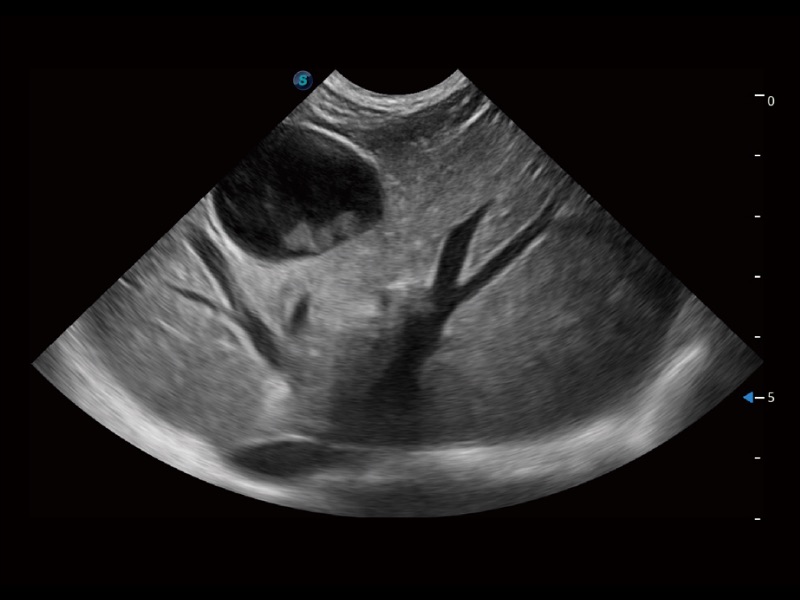

大型犬、馬科、農(nóng)場動(dòng)物及大型異寵動(dòng)物

ProPet 70專為動(dòng)物醫(yī)生設(shè)計(jì),對不同的動(dòng)物體型和生理結(jié)構(gòu)作出了針對性的優(yōu)化。通過動(dòng)物影像專用軟件,可滿足個(gè)性化的應(yīng)用需求,幫助動(dòng)物醫(yī)生獲得更精確的診斷數(shù)據(jù)。

ProPet 70 全新的動(dòng)物超聲智能軟件和豐富的探頭群,為動(dòng)物醫(yī)生提供了高清晰度和精細(xì)分辨率的圖像,無論在寵物、馬科、畜牧還是實(shí)驗(yàn)室動(dòng)物等應(yīng)用中都可以輕松應(yīng)對,為您的日常工作帶來滿意的體驗(yàn)。